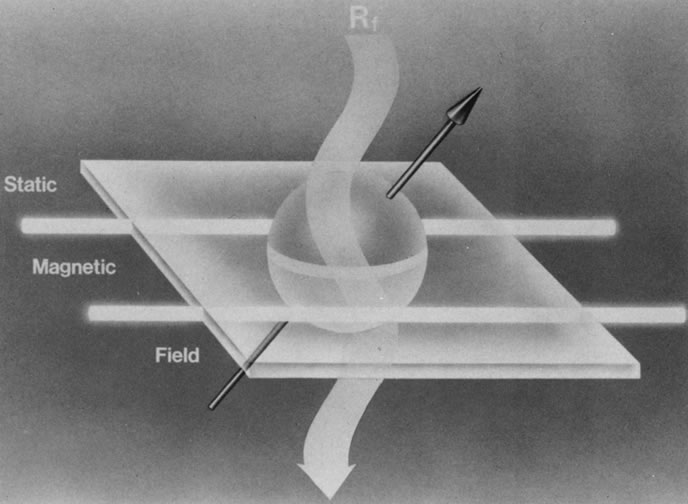

When a properly tuned pulse of RF energy is applied to the tissues in the static magnetic field, the nuclei absorb energy and can shift from parallel to antiparallel alignment (Fig. 4). The energized nuclei are said to “resonate” as they flip to a higher energy state. The duration and amplitude of the RF pulse determine the degree of change of the magnetic moment of each nucleus and the direction of the net magnetic vector. When the RF pulse is turned off, the nuclei “relax” and return to the equilibrium state with the net magnetic vector again parallel in alignment to the direction of the static magnetic field (Fig. 5). The energy released as the nuclei realign at the lower energy state is received as an RF signal by a receiver RF coil, and this signal is processed by a computer to generate an image.1,5,8,12,14